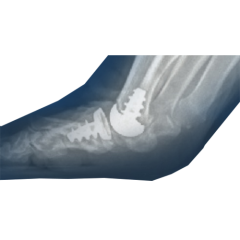

Explore our broad range ofOrthopedic Products

We are dedicated to improving the quality of life of patients suffering with bone and joint problems by delivering the latest medical devices that are proven to be effective and backed by scientific studies and research

• Surgical Devices